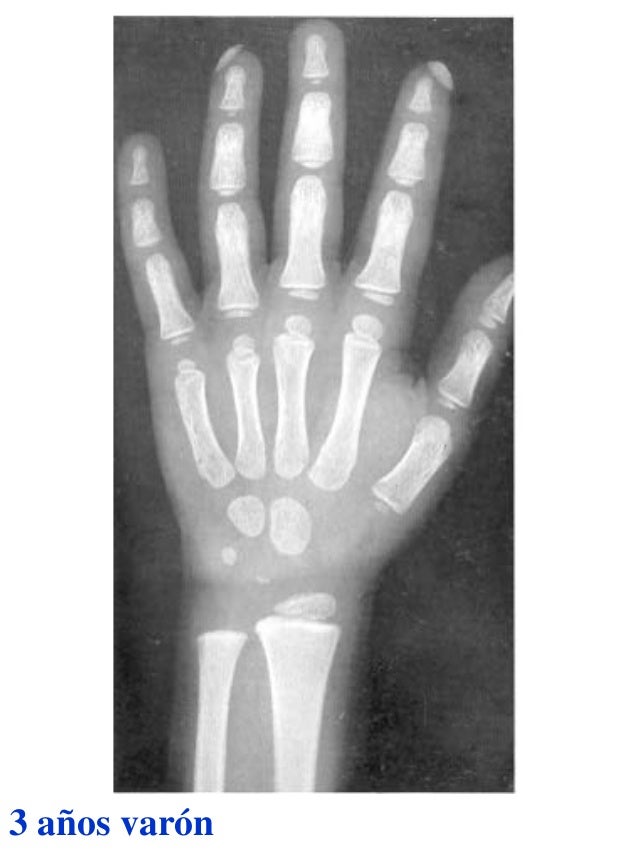

Tablas De Greulich Y Pyle The standards established by greulich and pyle, undoubtedly the most popular method, consist of two series of standard plates. The standards established by greulich and pyle, undoubtedly the most popular method, consist of two series of standard plates. El documento lista las edades. This systematic review summarizes the. The greulich and pyle method is one of the two main ways to assess the bone age of children. Both main methods of bone age. Scribd is the world's largest social reading and publishing site. 153 recomendaciones • 616,869 vistas. Atlas greulich y pyle | pdf | descarga gratuita. The greulich and pyle atlas is used to estimate the age of children and adolescents. The radiographic atlas of skeletal development of the hand and wrist by ww greulich and si pyle is a classic radiological.

Atlas greulich y pyle Tablas De Greulich Y Pyle The standards established by greulich and pyle, undoubtedly the most popular method, consist of two series of standard plates. Atlas greulich y pyle | pdf | descarga gratuita. Scribd is the world's largest social reading and publishing site. 153 recomendaciones • 616,869 vistas. The radiographic atlas of skeletal development of the hand and wrist by ww greulich and si pyle. Tablas De Greulich Y Pyle.

Atlas greulich y pyle Tablas De Greulich Y Pyle Both main methods of bone age. 153 recomendaciones • 616,869 vistas. The greulich and pyle method is one of the two main ways to assess the bone age of children. The standards established by greulich and pyle, undoubtedly the most popular method, consist of two series of standard plates. Scribd is the world's largest social reading and publishing site. This. Tablas De Greulich Y Pyle.